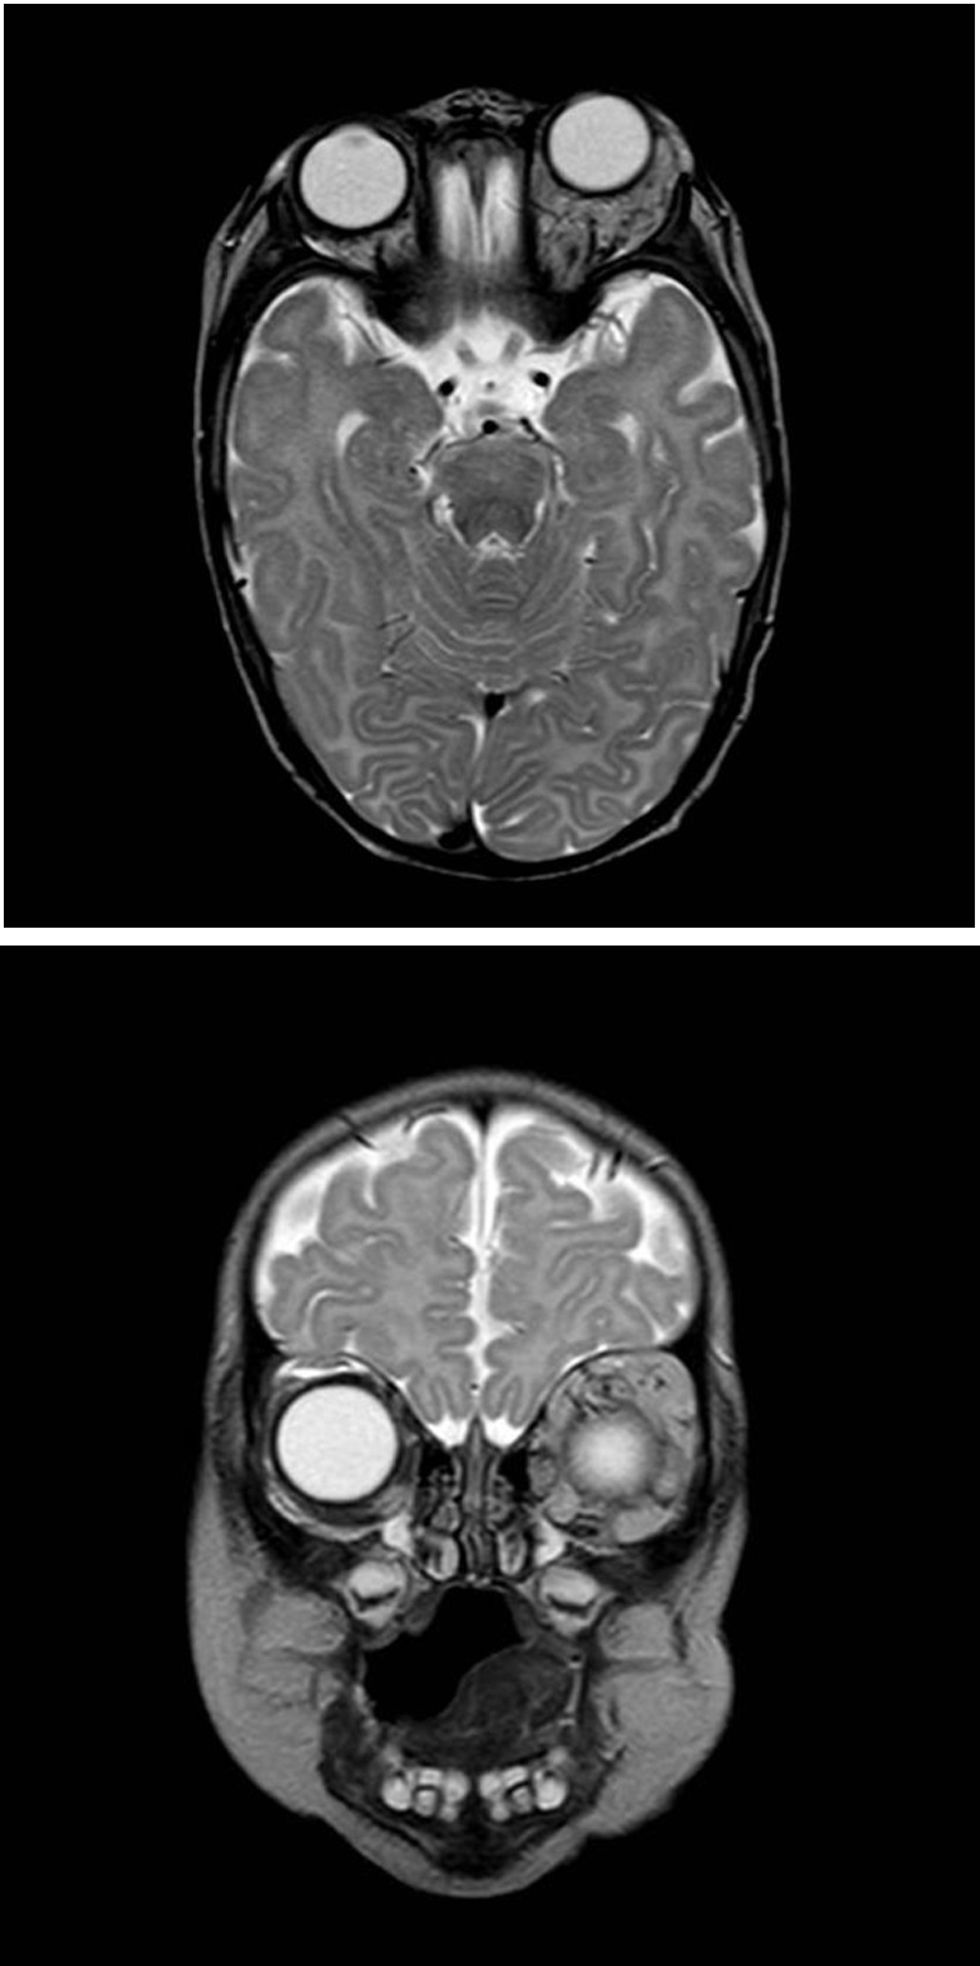

An MRI scan (Fig. 2) showed a predominantly intraconal retrobulbar lobulated lesion with an irregular shape and multiple dilated vessels, consistent with an infantile hemangioma, without intracranial extension.